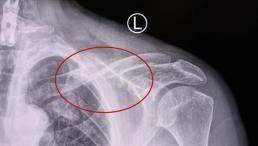

西安医学院三附院高难度封堵术让六旬患者告别反复头晕头痛

阳光讯(记者 郑亚雷)“折磨人十年的头晕头痛终于好了!现在脑袋清清爽爽,太感谢吕安林院长和他的团队了!” 67岁的方先生来自山西,脸上洋溢着久违的轻松笑容。困扰他十年的反复头痛、头昏症状,在西安医学院...